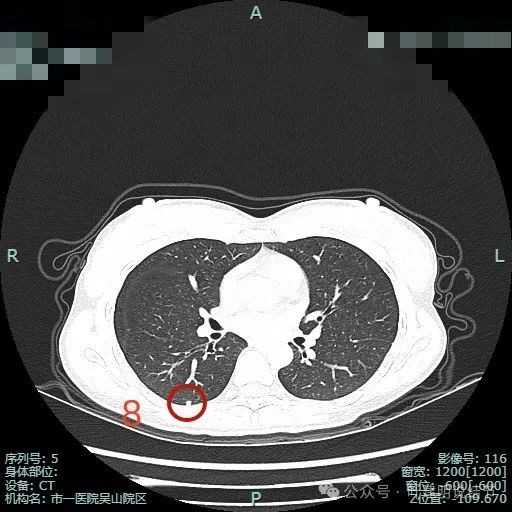

病灶8:右下叶小结节,整体轮廓较清,密度较高,考虑良性的可能性大些。